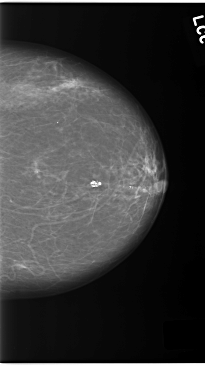

C_0140_1.LEFT_MLO

LEFT_MLO LINES 5800 PIXELS_PER_LINE 4008 BITS_PER_PIXEL 12 RESOLUTION 50 NON_OVERLAY